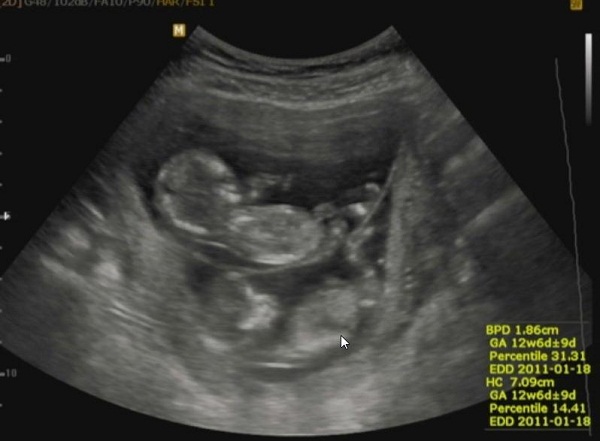

Volt szo arrol, hogy hianyoljatok kisgaby iker parjabol a masik lurkot.

Nos, akkor a buszke apakent megosztanam ezt a kepet:

Kép

büszke apuka,köszi a fotót,tökéletesen látszik a két babóca :lol: nagyon szépek!!!és üdv itt közöttünk.

garfield, Gratulálok a két kis csöppséghez! Büszke is lehetsz,nagyon szépek!

Nekem a képről vizipók jutott eszemben, ahogy a nyugágyon fekszik, csak itt kettő van.. :lol: :lol: :lol: Tündériek! Jó, hogy felraktad! :D

Garfield, Kisgaby, köszönjük az élményt. Bevallom,még soha nem láttam ikres UHU képet. Csodálatosak :lol:

Kisgaby! Garfield!

Eeeez igen!!! Ez az idill!!! El is hiszem, hogy büszkék Vagytok! Gyönyörüek!!!!